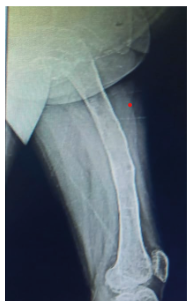

Figure 3. Lateral radiograph of the left femur: poor bone quality, very thin cortices, ground-glass images, areas of osteolysis and osteosclerosis in the greater and lesser trochanters and the neck of the femur, loss of distinction between the cortex and the bone marrow of the upper part of the femur.

Figure 4. Lateral radiograph of the left knee and leg: evidence of valgus deformity